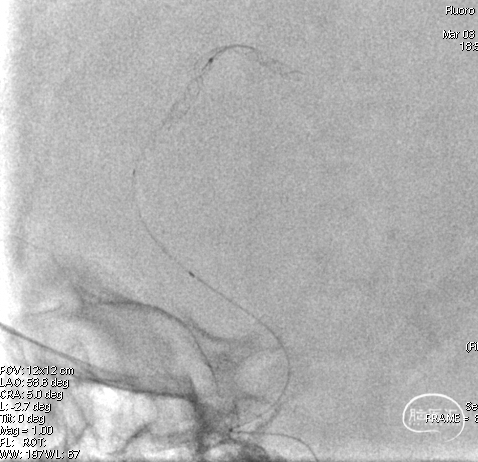

在泥鳅导丝引导下,同轴将远端通路导管输送到左椎V1段,撤出泥鳅导丝,选择工作角度后,再次入路造影。

在微导丝引导下,将血流导向密网支架专用微导管缓慢顺利通过左侧小脑后下动脉瘤,放入动脉瘤远端,撤出微导丝,再次手推造影确认真腔。

将血流导向密网支架经微导管同轴通过动脉瘤,缓慢撤微导管释放血流导向密网支架,全程放完后,再次造影确定支架内血流通畅。

再次行全脑血管造影,见血流灌注良好、通畅,退出导管。